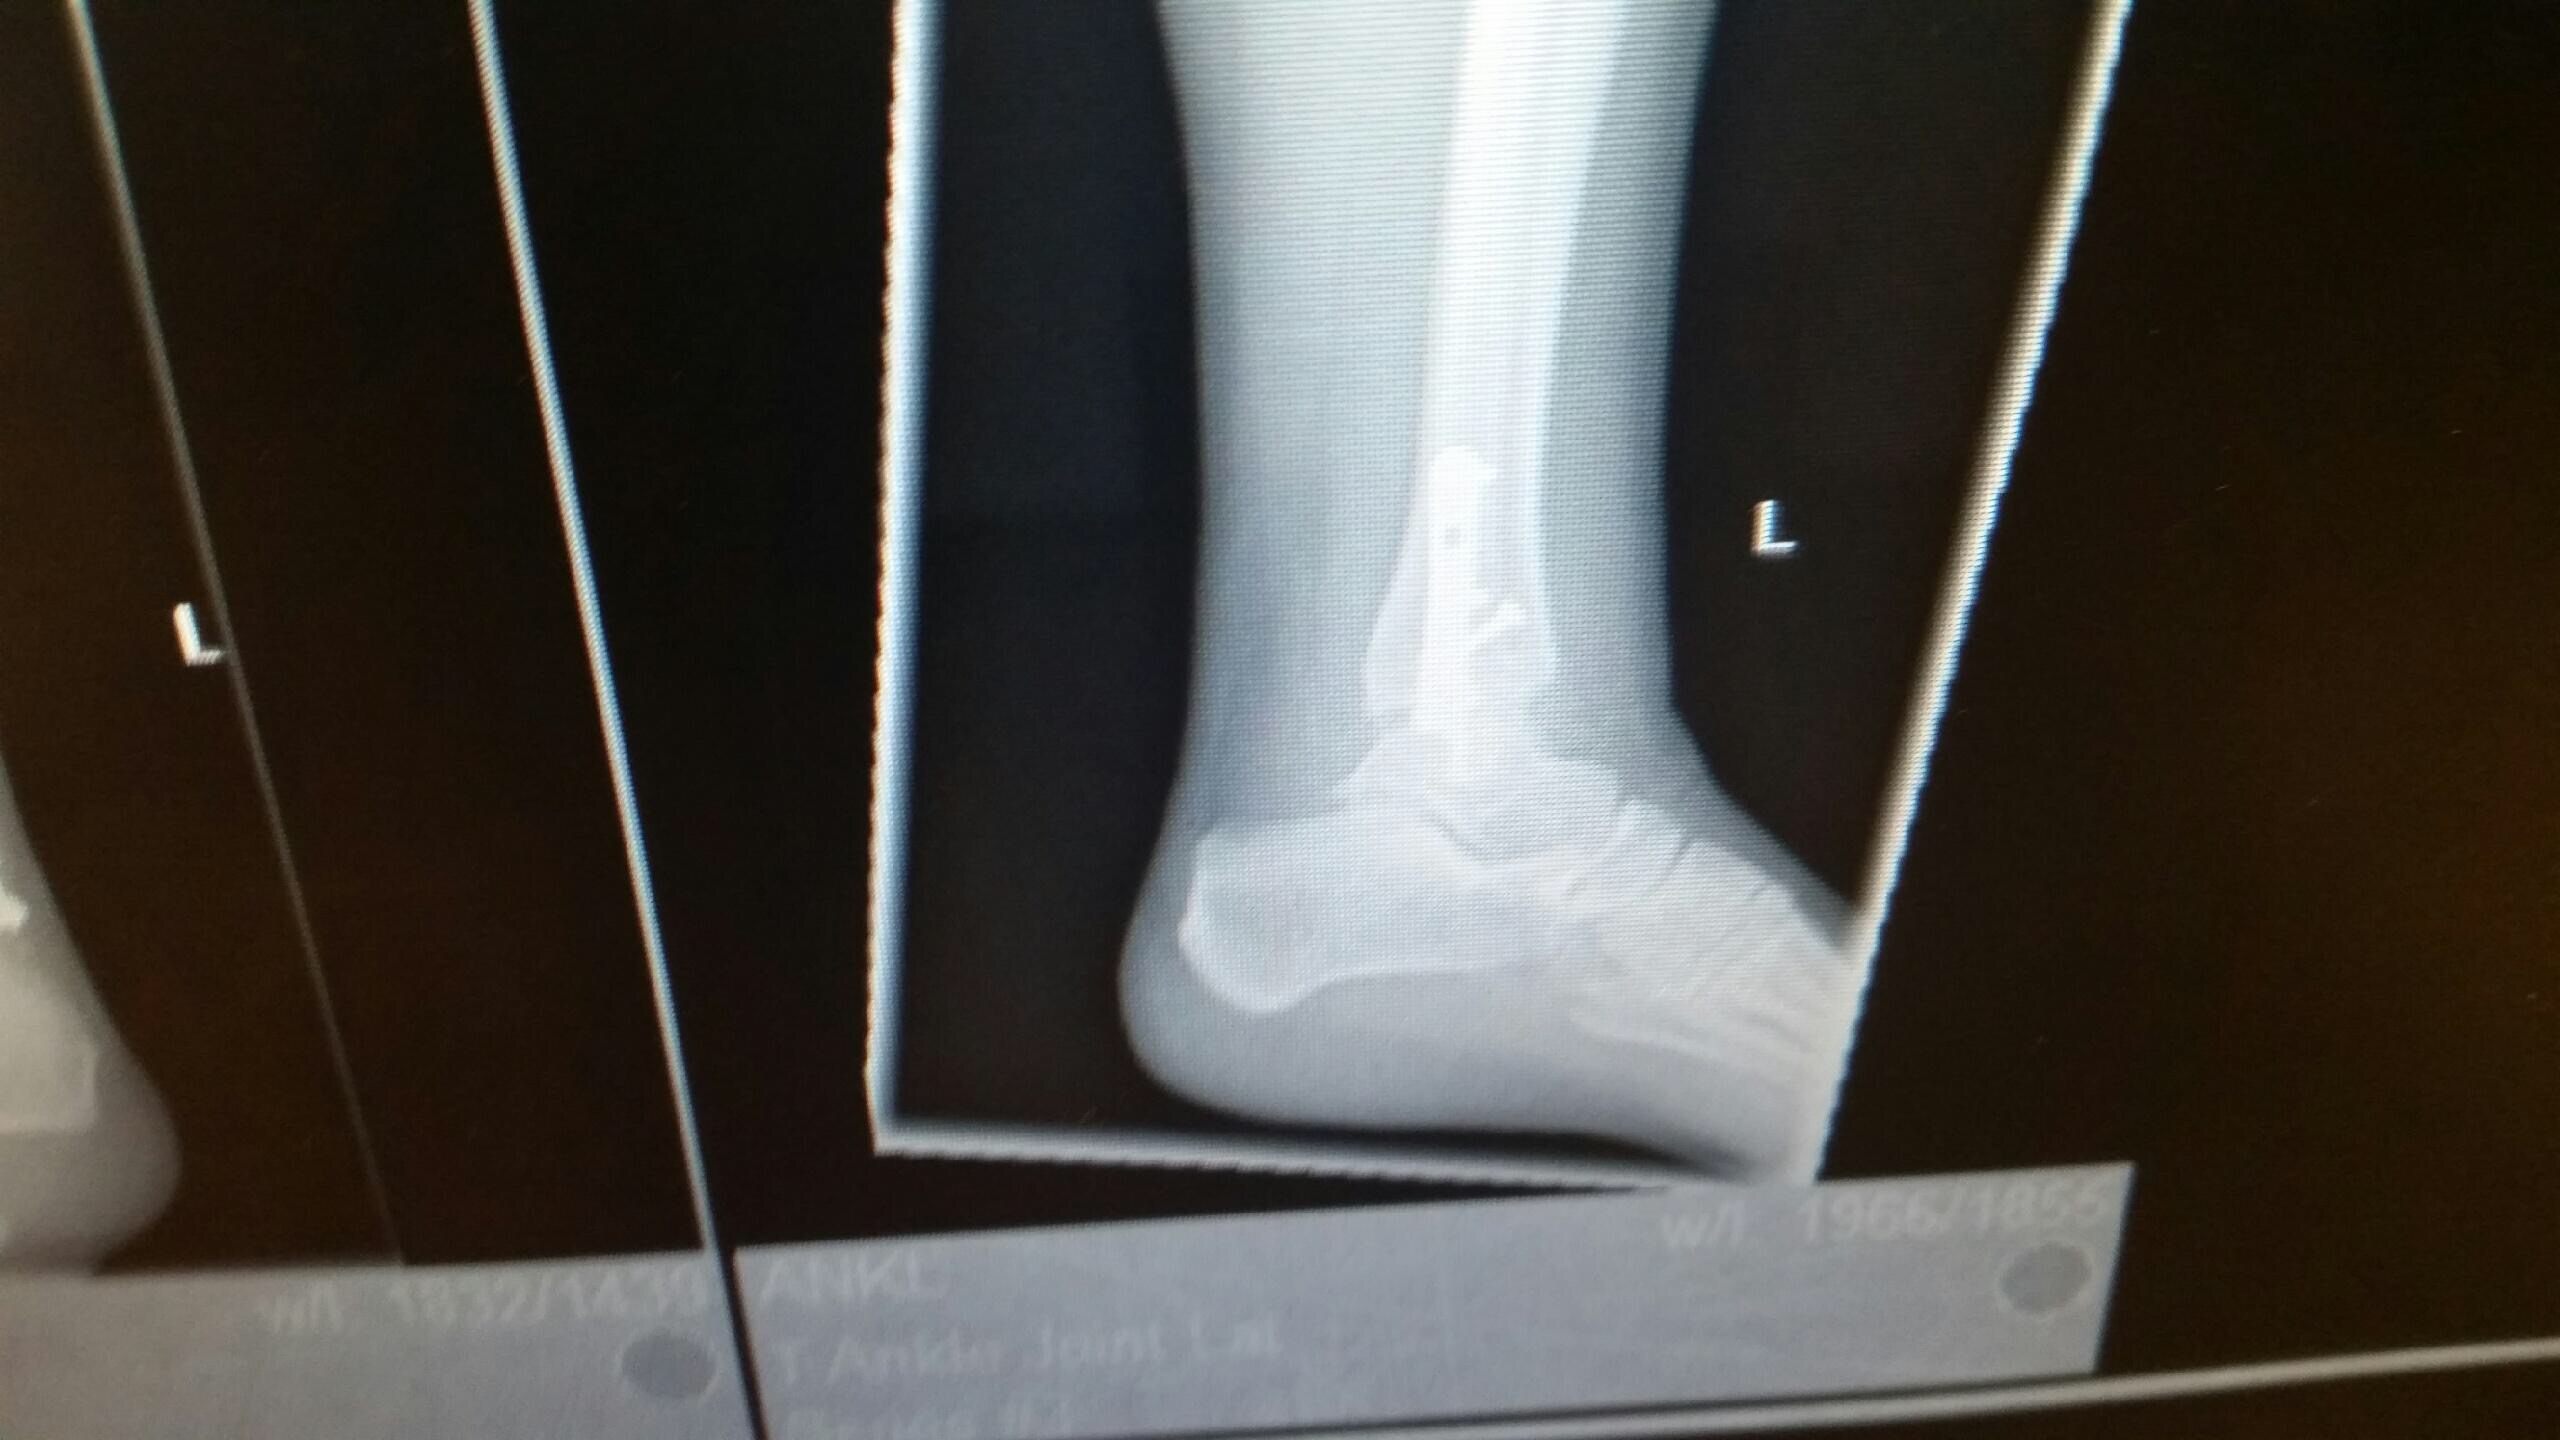

The cast is off! I can’t walk on my ankle for two more weeks, but I can move it a bit. The stitches were removed and I can get the incisions wet and everything! There were twelve stitches on the outside and six on the inside of my ankle. The swelling and bruising isn’t as bad as I thought it would be. It’s kind of scary to have this unprotected ankle, but encouraging to see how much I can move it. I feel like I’m really making progress.